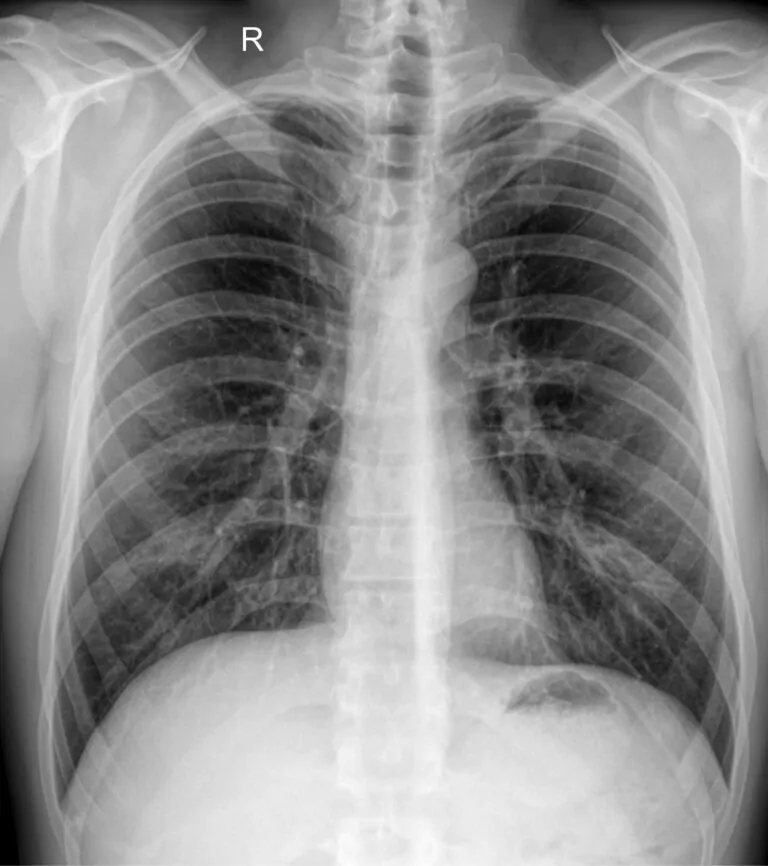

Флюорография СПб представляет собой метод рентгенологического исследования органов грудной клетки, который применяется для раннего выявления заболеваний легких и других патологий. Данный вид диагностики широко используется в профилактической медицине и позволяет обнаружить изменения на ранних стадиях, когда симптомы могут отсутствовать или быть слабо выраженными.

Флюорография основана на использовании рентгеновского излучения, которое проходит через ткани организма и фиксируется на специальном носителе. Полученное изображение позволяет врачу оценить состояние органов грудной клетки.